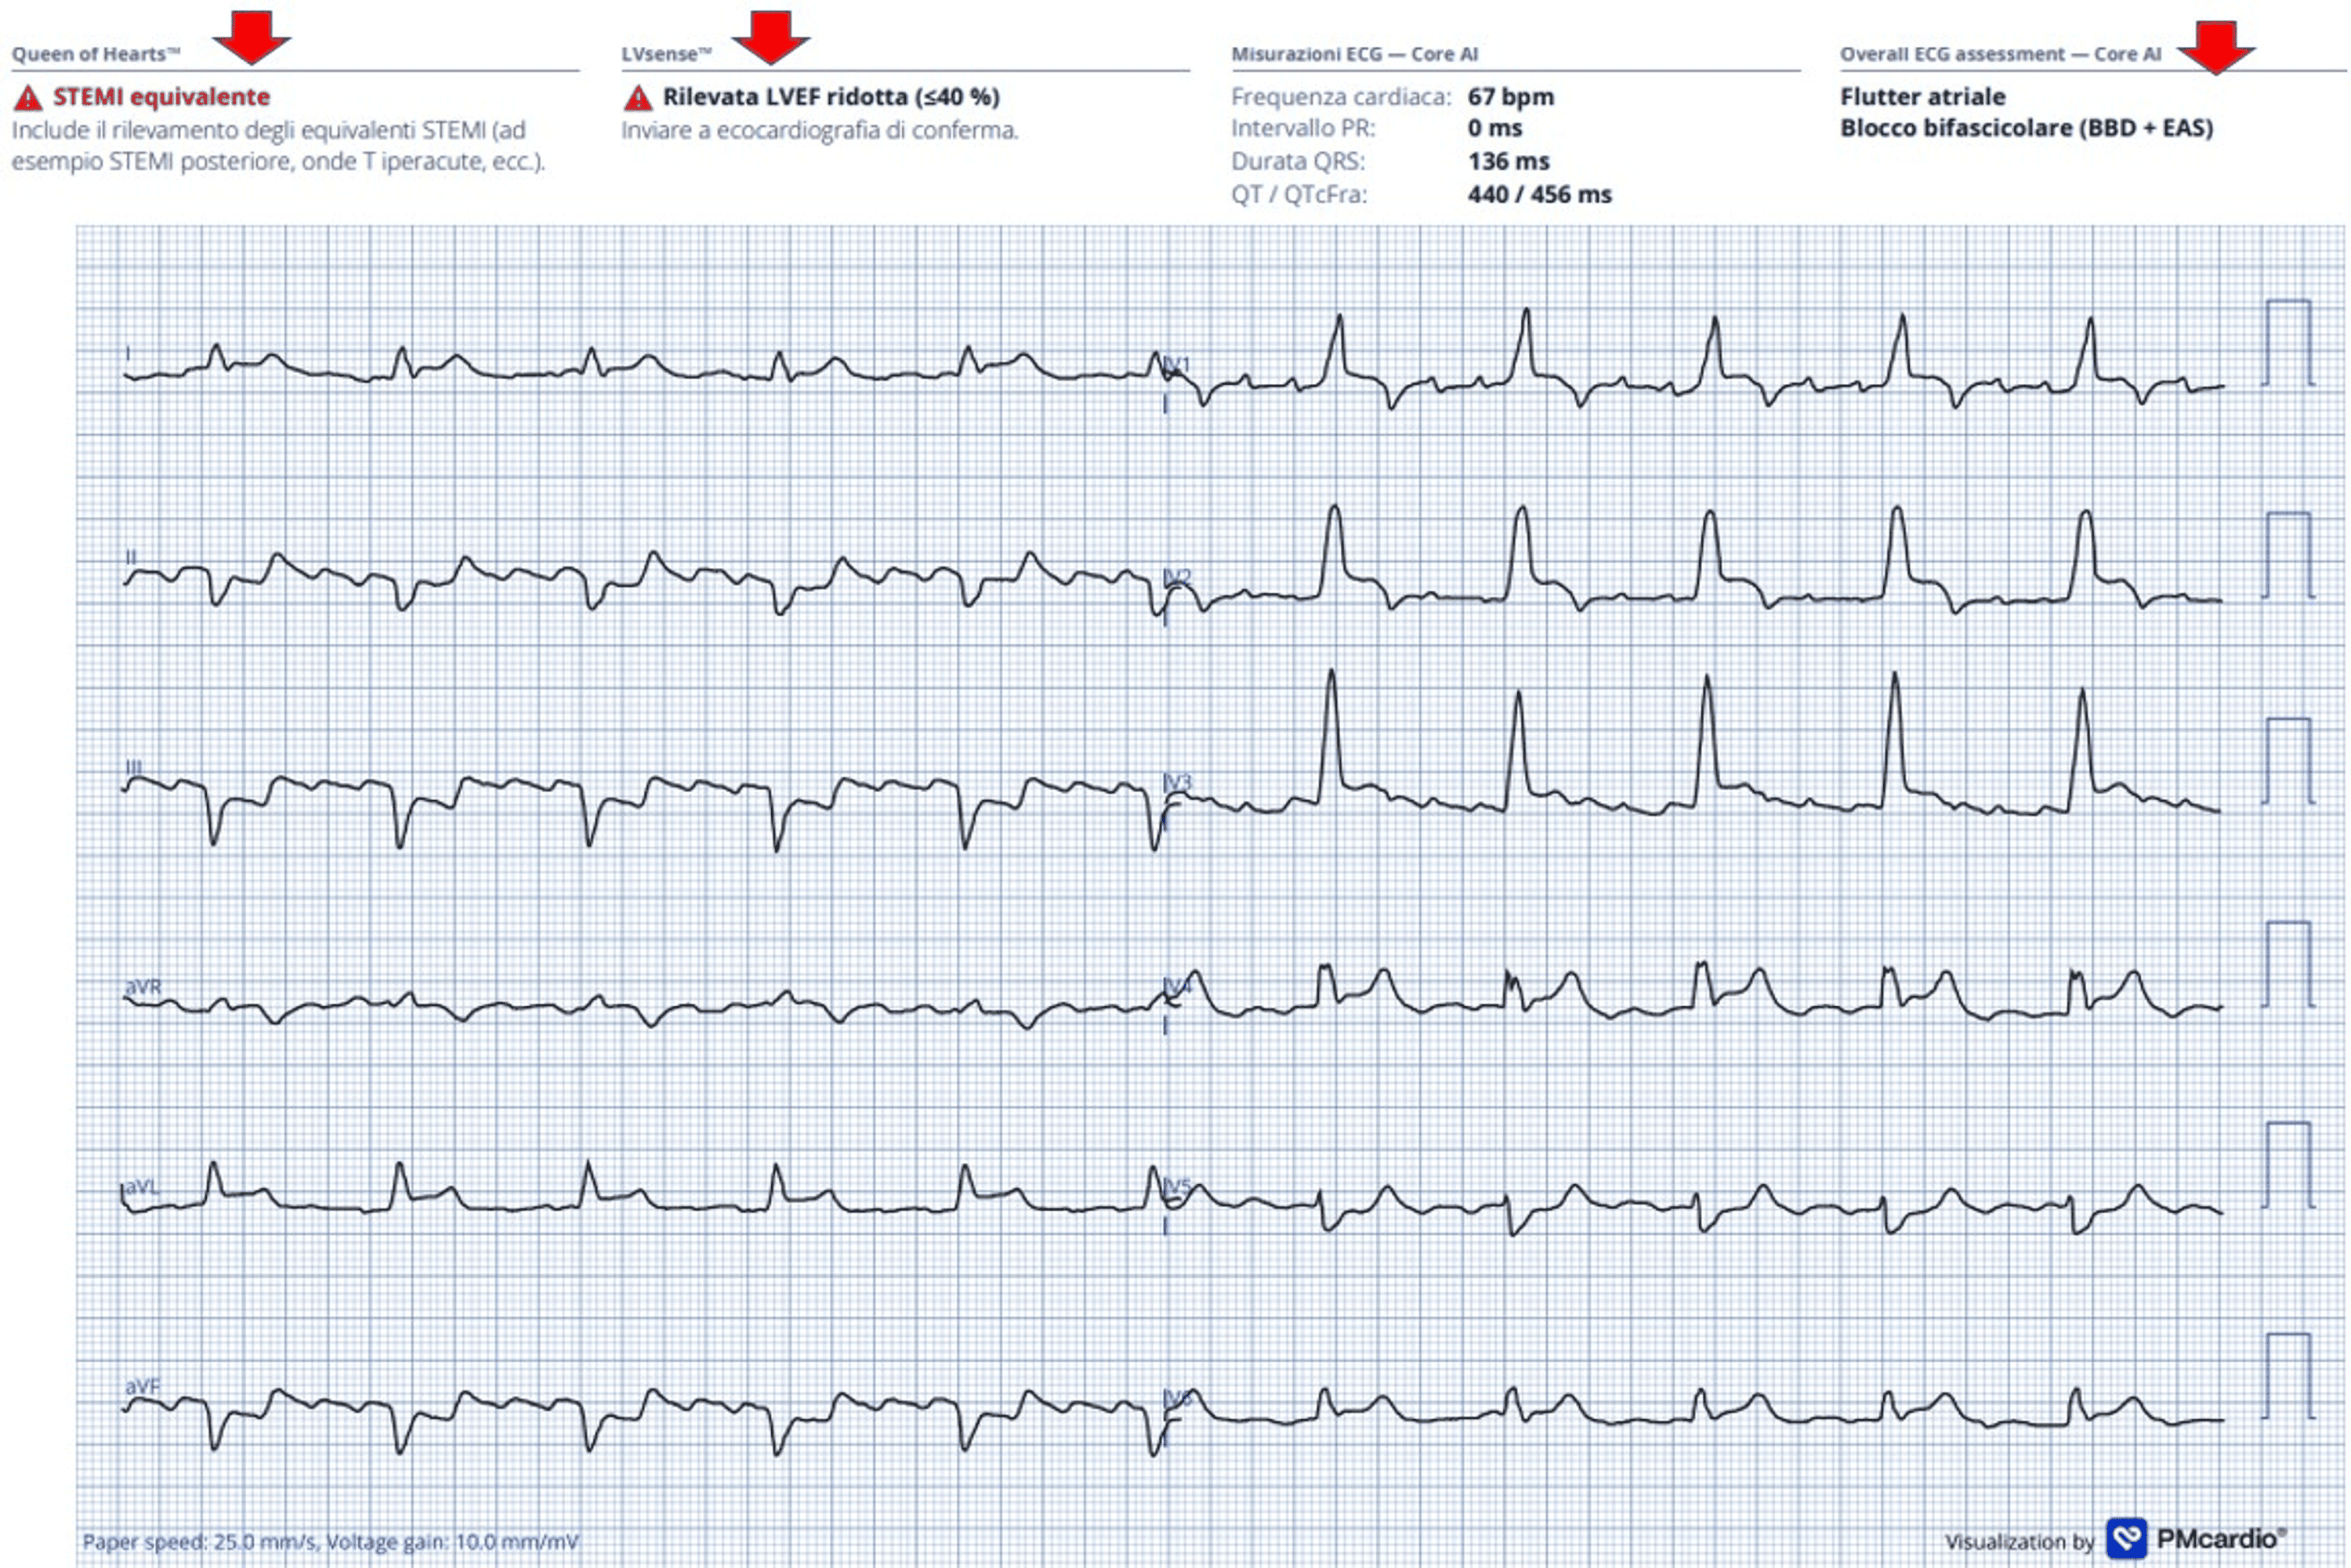

This single-patient case report describes an elderly man presenting with chest pain, hypotension, and bifascicular block (BFB)—a combination of right bundle branch block (RBBB) and left anterior fascicular block (LAFB)—whose ECG showed QRS‑concordant anterior and lateral ST‑segment elevation consistent with a STEMI‑equivalent / occlusive myocardial infarction (OMI) pattern. Urgent coronary angiography revealed a long, severely calcified, near‑occlusive proximal left anterior descending (LAD) artery lesion, successfully treated with primary PCI and drug‑eluting stent implantation, achieving TIMI 3 flow. The Queen of Hearts (PMcardio) AI‑based smartphone app correctly classified the ECG as STEMI‑equivalent, identified atrial flutter and BFB, and predicted reduced left ventricular ejection fraction, later confirmed by echocardiography (EF 38%). This case highlights BFB with concordant anterior ST elevation as a high-risk marker of proximal LAD culprit OMI and provides anecdotal evidence that specialized AI-enabled ECG interpretation can support rapid and accurate decision-making in ACS.

The initial ECG (page 2) showed atrial flutter with 4:1 AV conduction, complete RBBB, LAFB, and QRS‑concordant ST‑segment elevation in V1–V4 with additional lateral ST elevation (I, aVL, V6) and reciprocal inferior changes, leading to a working diagnosis of anterolateral STEMI in the context of new or presumably new BFB. A second ECG (page 3) demonstrated further progression of anterior ST elevation. The Queen of Hearts app labeled the tracing as STEMI‑equivalent, detected the bifascicular block and atrial flutter, and predicted an EF <40%. Coronary angiography (page 4 and Video 1) revealed a severely calcified, near‑occlusive proximal LAD stenosis, treated successfully with drug‑eluting stent implantation and restoration of TIMI 3 flow; other coronary vessels showed only mild, non‑obstructive disease. Post‑PCI ECG (page 5) showed persistence of BFB but resolution of ST elevation with QRS‑discordant T‑wave changes typical for RBBB. Laboratory testing demonstrated markedly elevated high‑sensitivity troponin I and NT‑proBNP with moderate anemia and chronic kidney disease (Table 1, page 6). Echocardiography (Video 2) confirmed apical akinesia, anterior/anteroseptal hypokinesia, EF 38%, biatrial enlargement, and moderate ischemic mitral regurgitation, consistent with the AI‑predicted LV dysfunction. The in-hospital course was uncomplicated, and the patient was discharged after eight days on optimized heart failure and antithrombotic therapy.